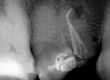

Una vez anestesiado y aislado se sigue la dirección que marca la CBCT hasta llegar a la cámara y localizar la gutapercha antigua. Para su retirada se usa el sistema RetreatAll® comenzando por la lima Zr1 (30/04, 21 mm) y la Zr2 (25/04 25 mm) a 500 rpm consiguiendo eliminar la gutapercha contaminada de los conductos previamente tratados de una manera segura.(Fig. 3)

Fig. 3: Imágenes de las limas Zr1 y Zr2 del sistema RetreatAll® empleadas durante el retratamiento para remover la

gutapercha contaminada del interior del sistema de conductos.